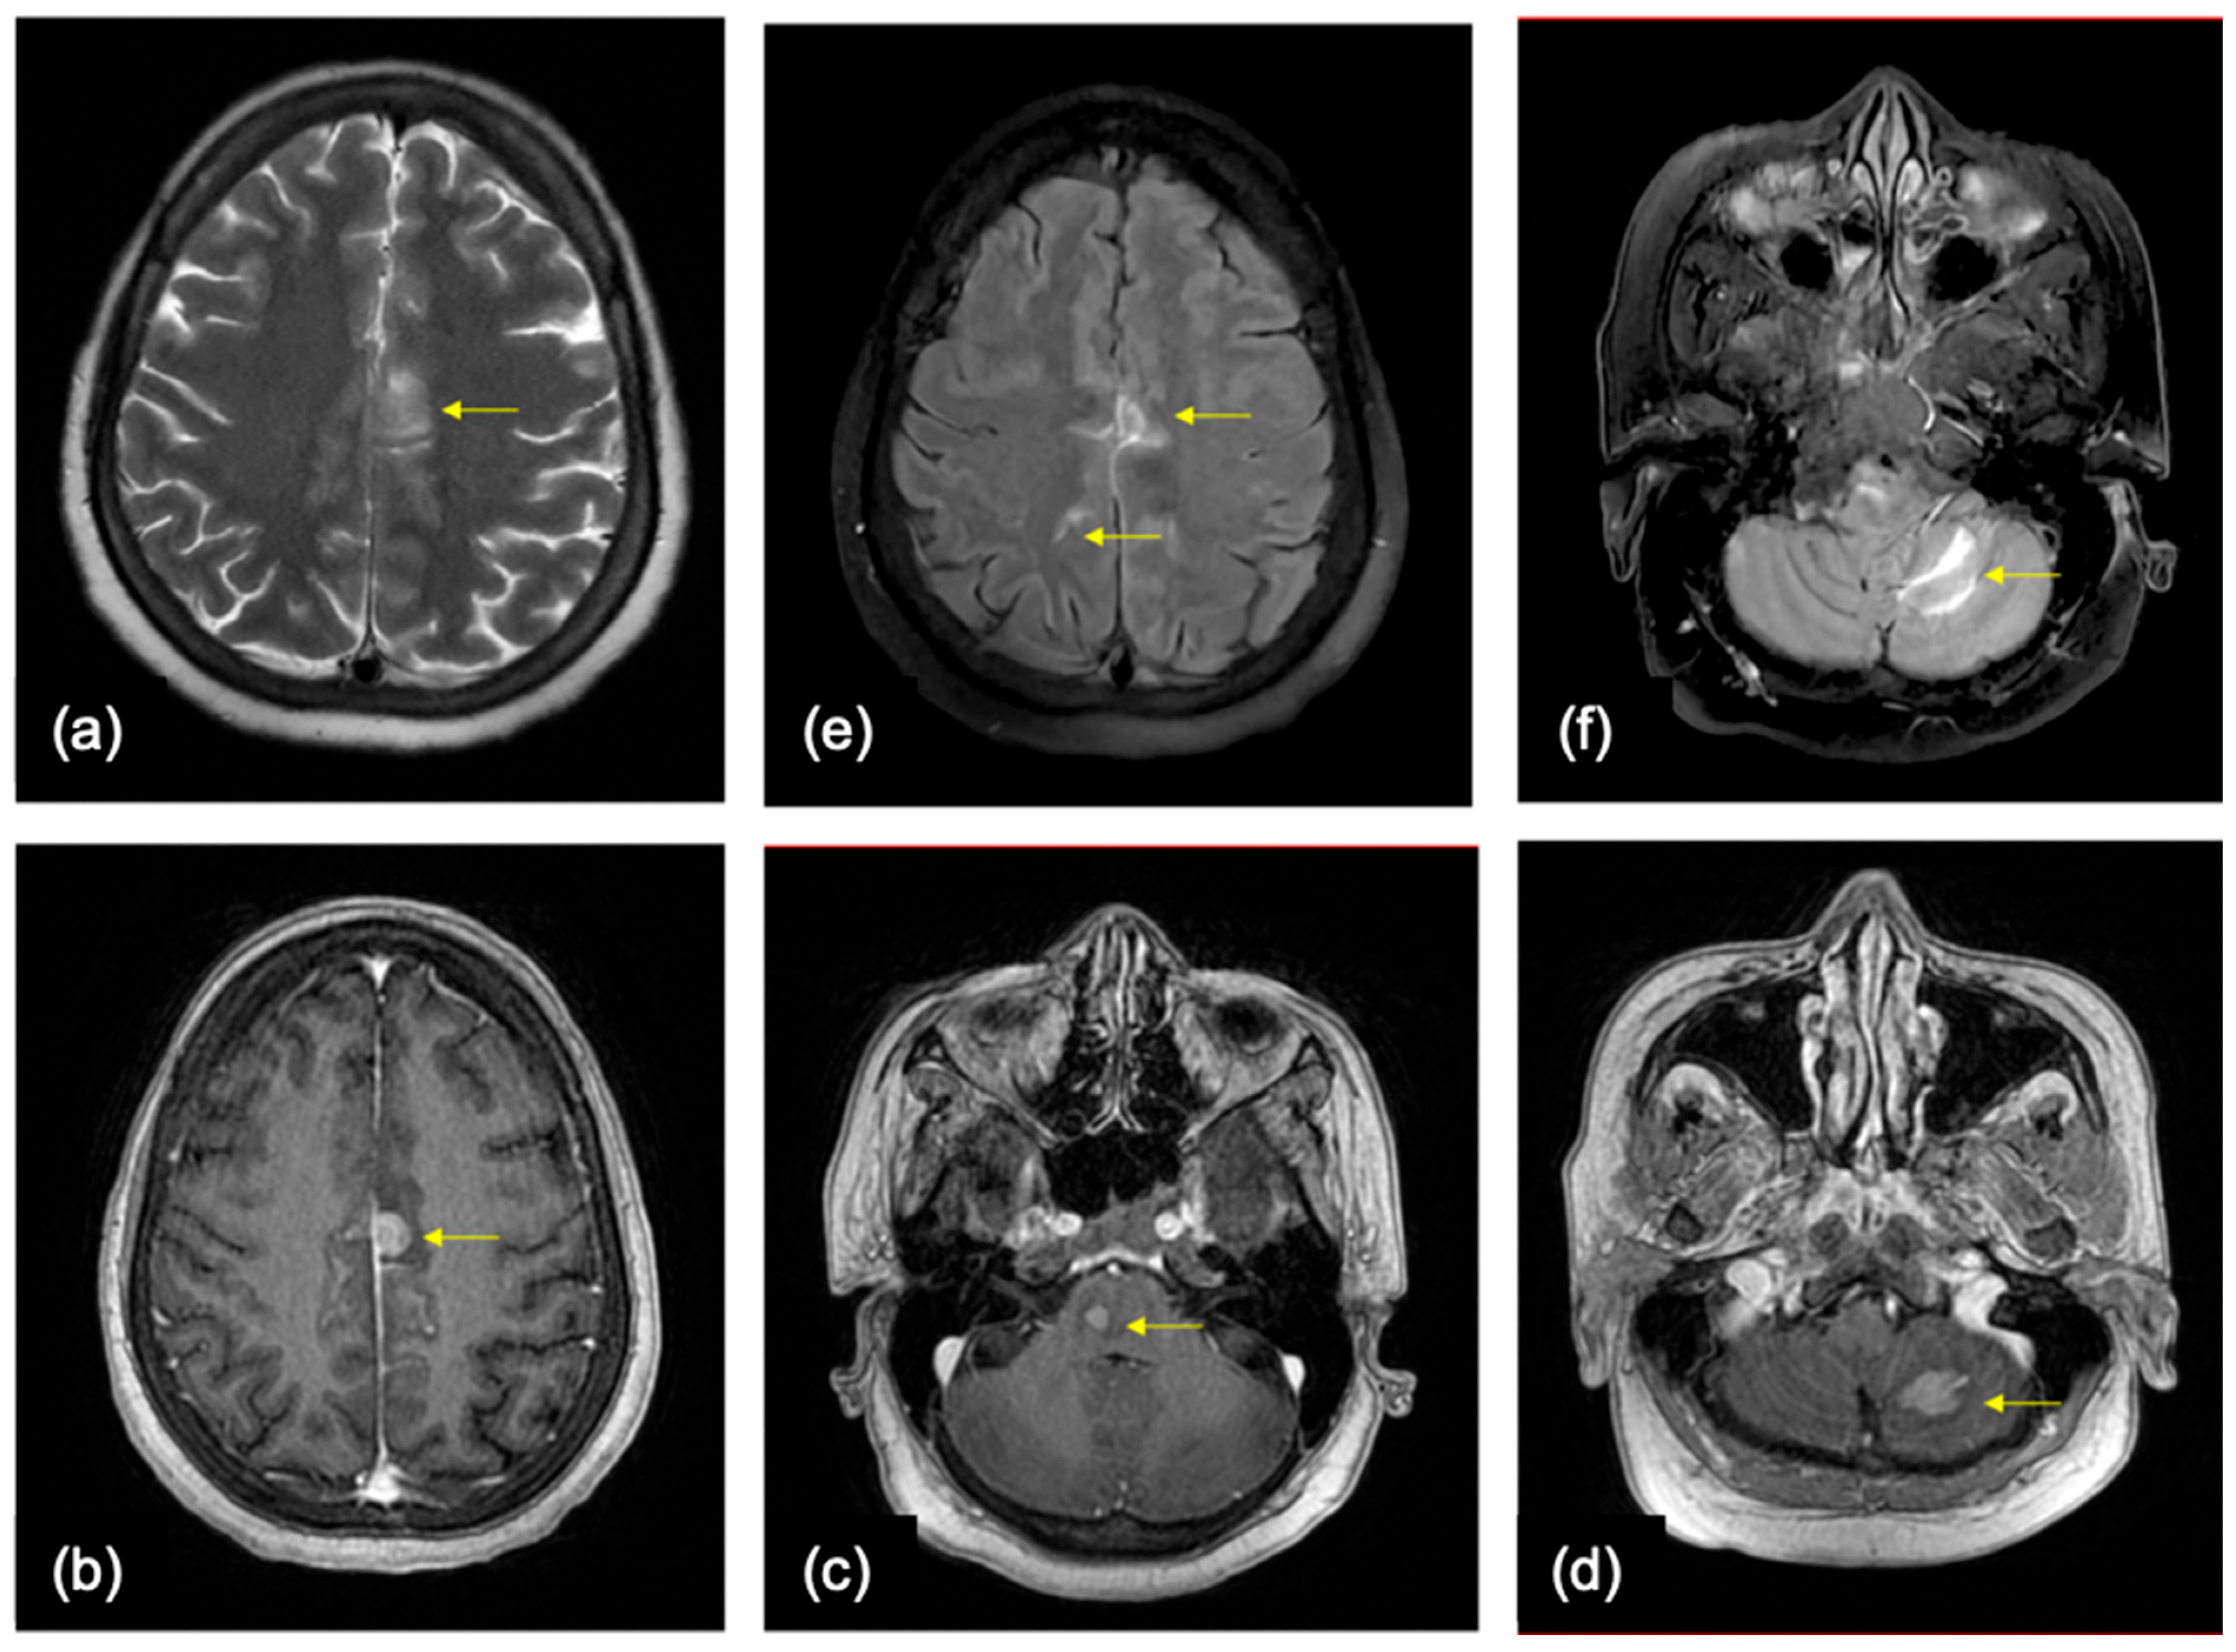

5.2. Role of Imaging in Diagnosis

7.1. Lung

7.2. Breast

7.3. Others